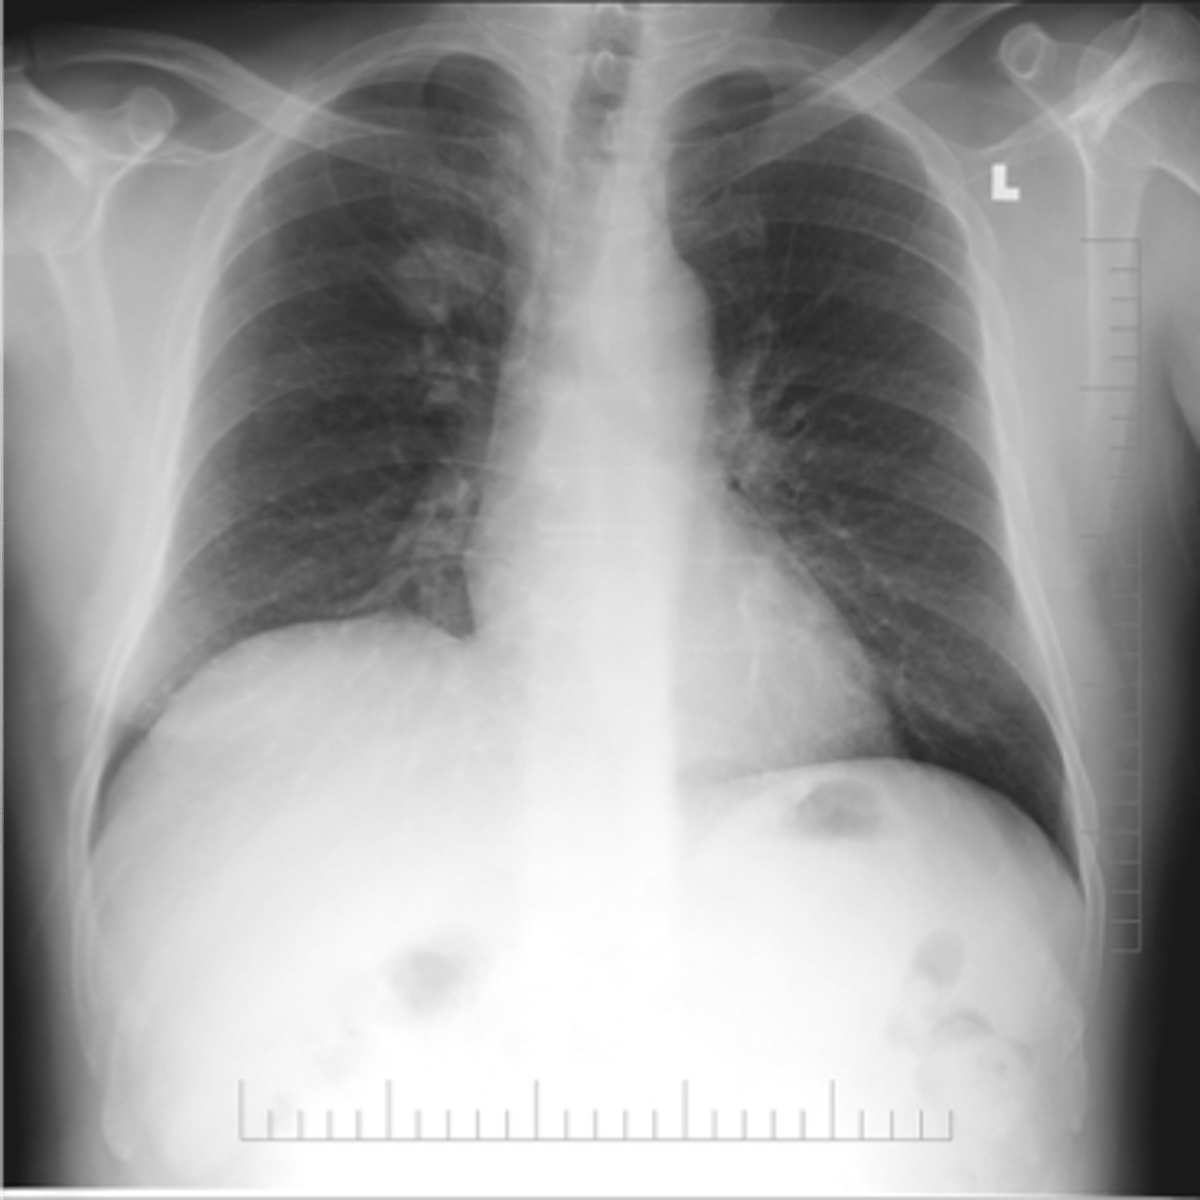

ARDS

ARDS